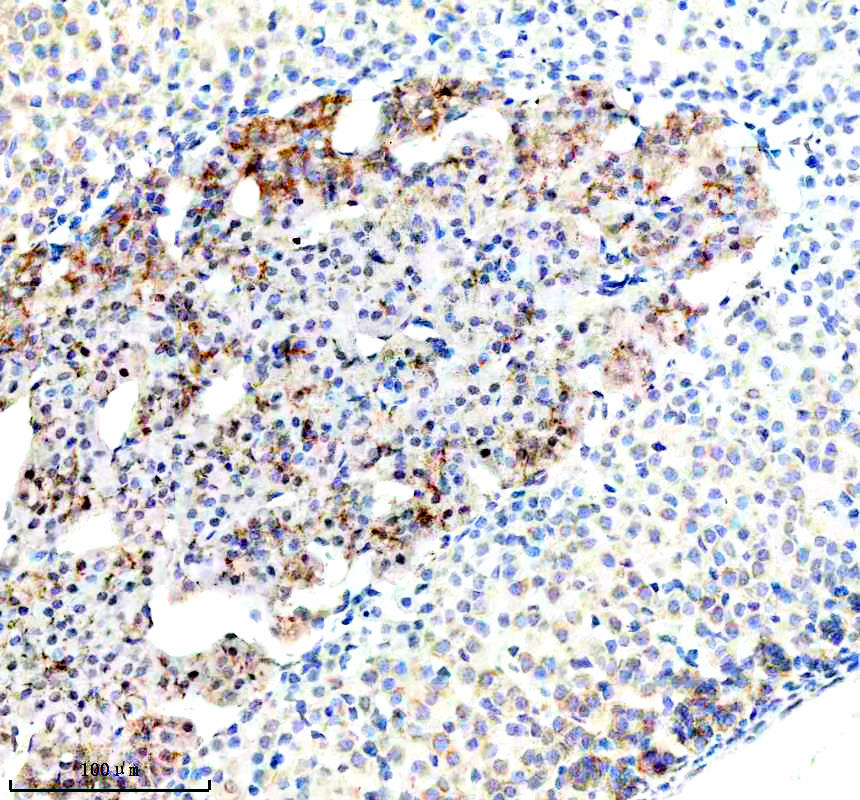

IHC analysis of BNIP3L using anti-BNIP3L antibody (BM5174) .

BNIP3L was detected in a paraffin-embedded section of human lymphoma tissue. The tissue section was incubated with rabbit anti-BNIP3L Antibody (BM5174) at a dilution of 1:200 and developed using HRP Conjugated Rabbit IgG Super Vision Assay Kit (Catalog # SV0002) with DAB (Catalog # AR1027) as the chromogen.

IHC analysis of BNIP3L using anti-BNIP3L antibody (BM5174) .

BNIP3L was detected in a paraffin-embedded section of human lymphoma tissue. The tissue section was incubated with rabbit anti-BNIP3L Antibody (BM5174) at a dilution of 1:200 and developed using HRP Conjugated Rabbit IgG Super Vision Assay Kit (Catalog # SV0002) with DAB (Catalog # AR1027) as the chromogen.